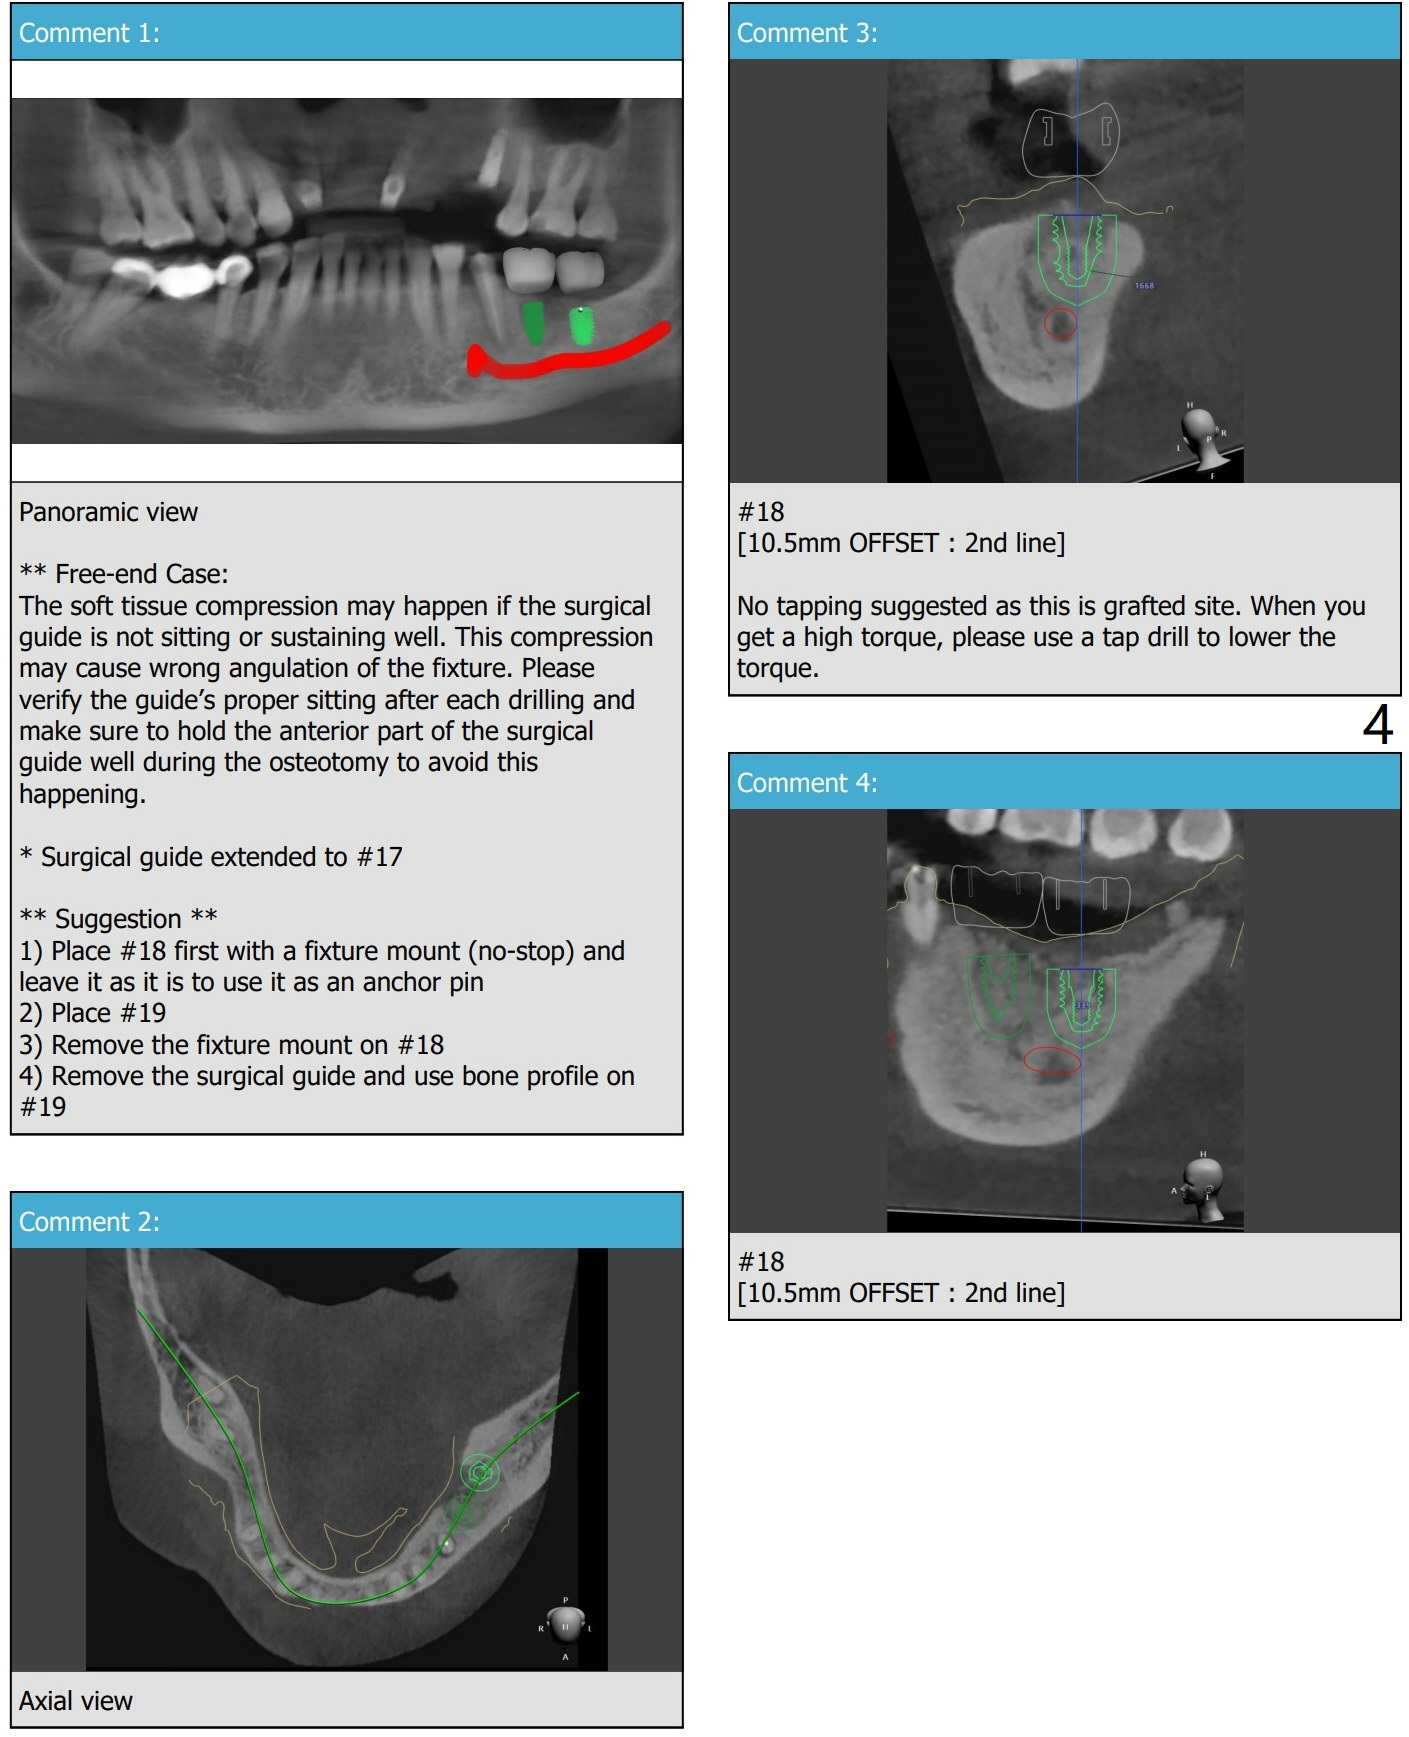

Distal Stop

5 months post socket preservation at 6